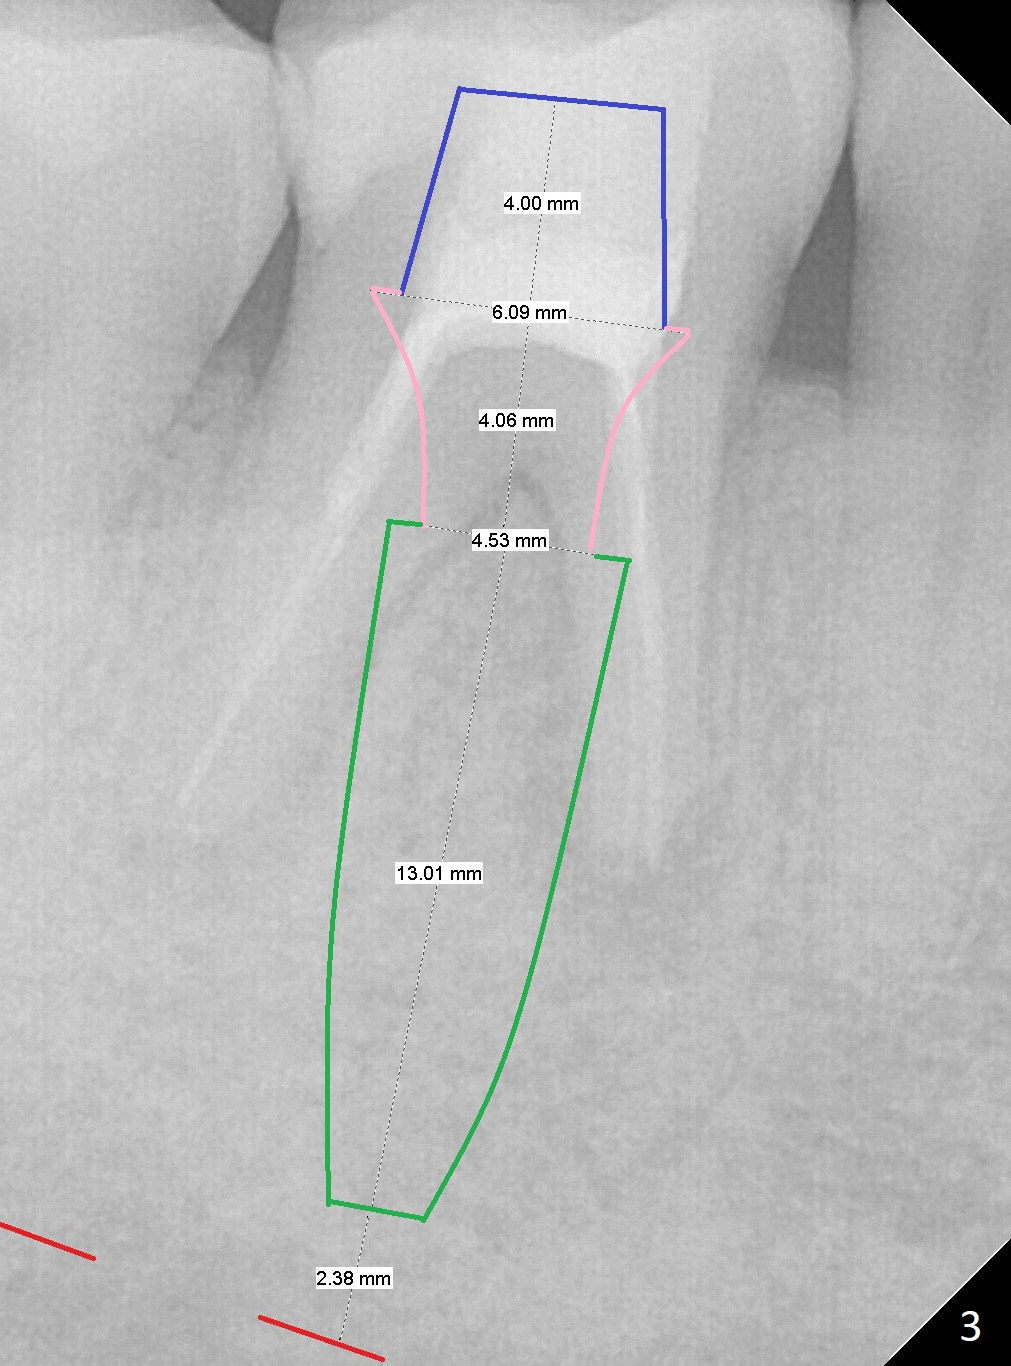

A 45-year-old man fractures the distolingual cusp of the tooth #30 subgingival (Fig.1). In fact RCT restores the septal bone, as compared to Fig.2. Initial depth at the septum is 13 mm (Fig.3).